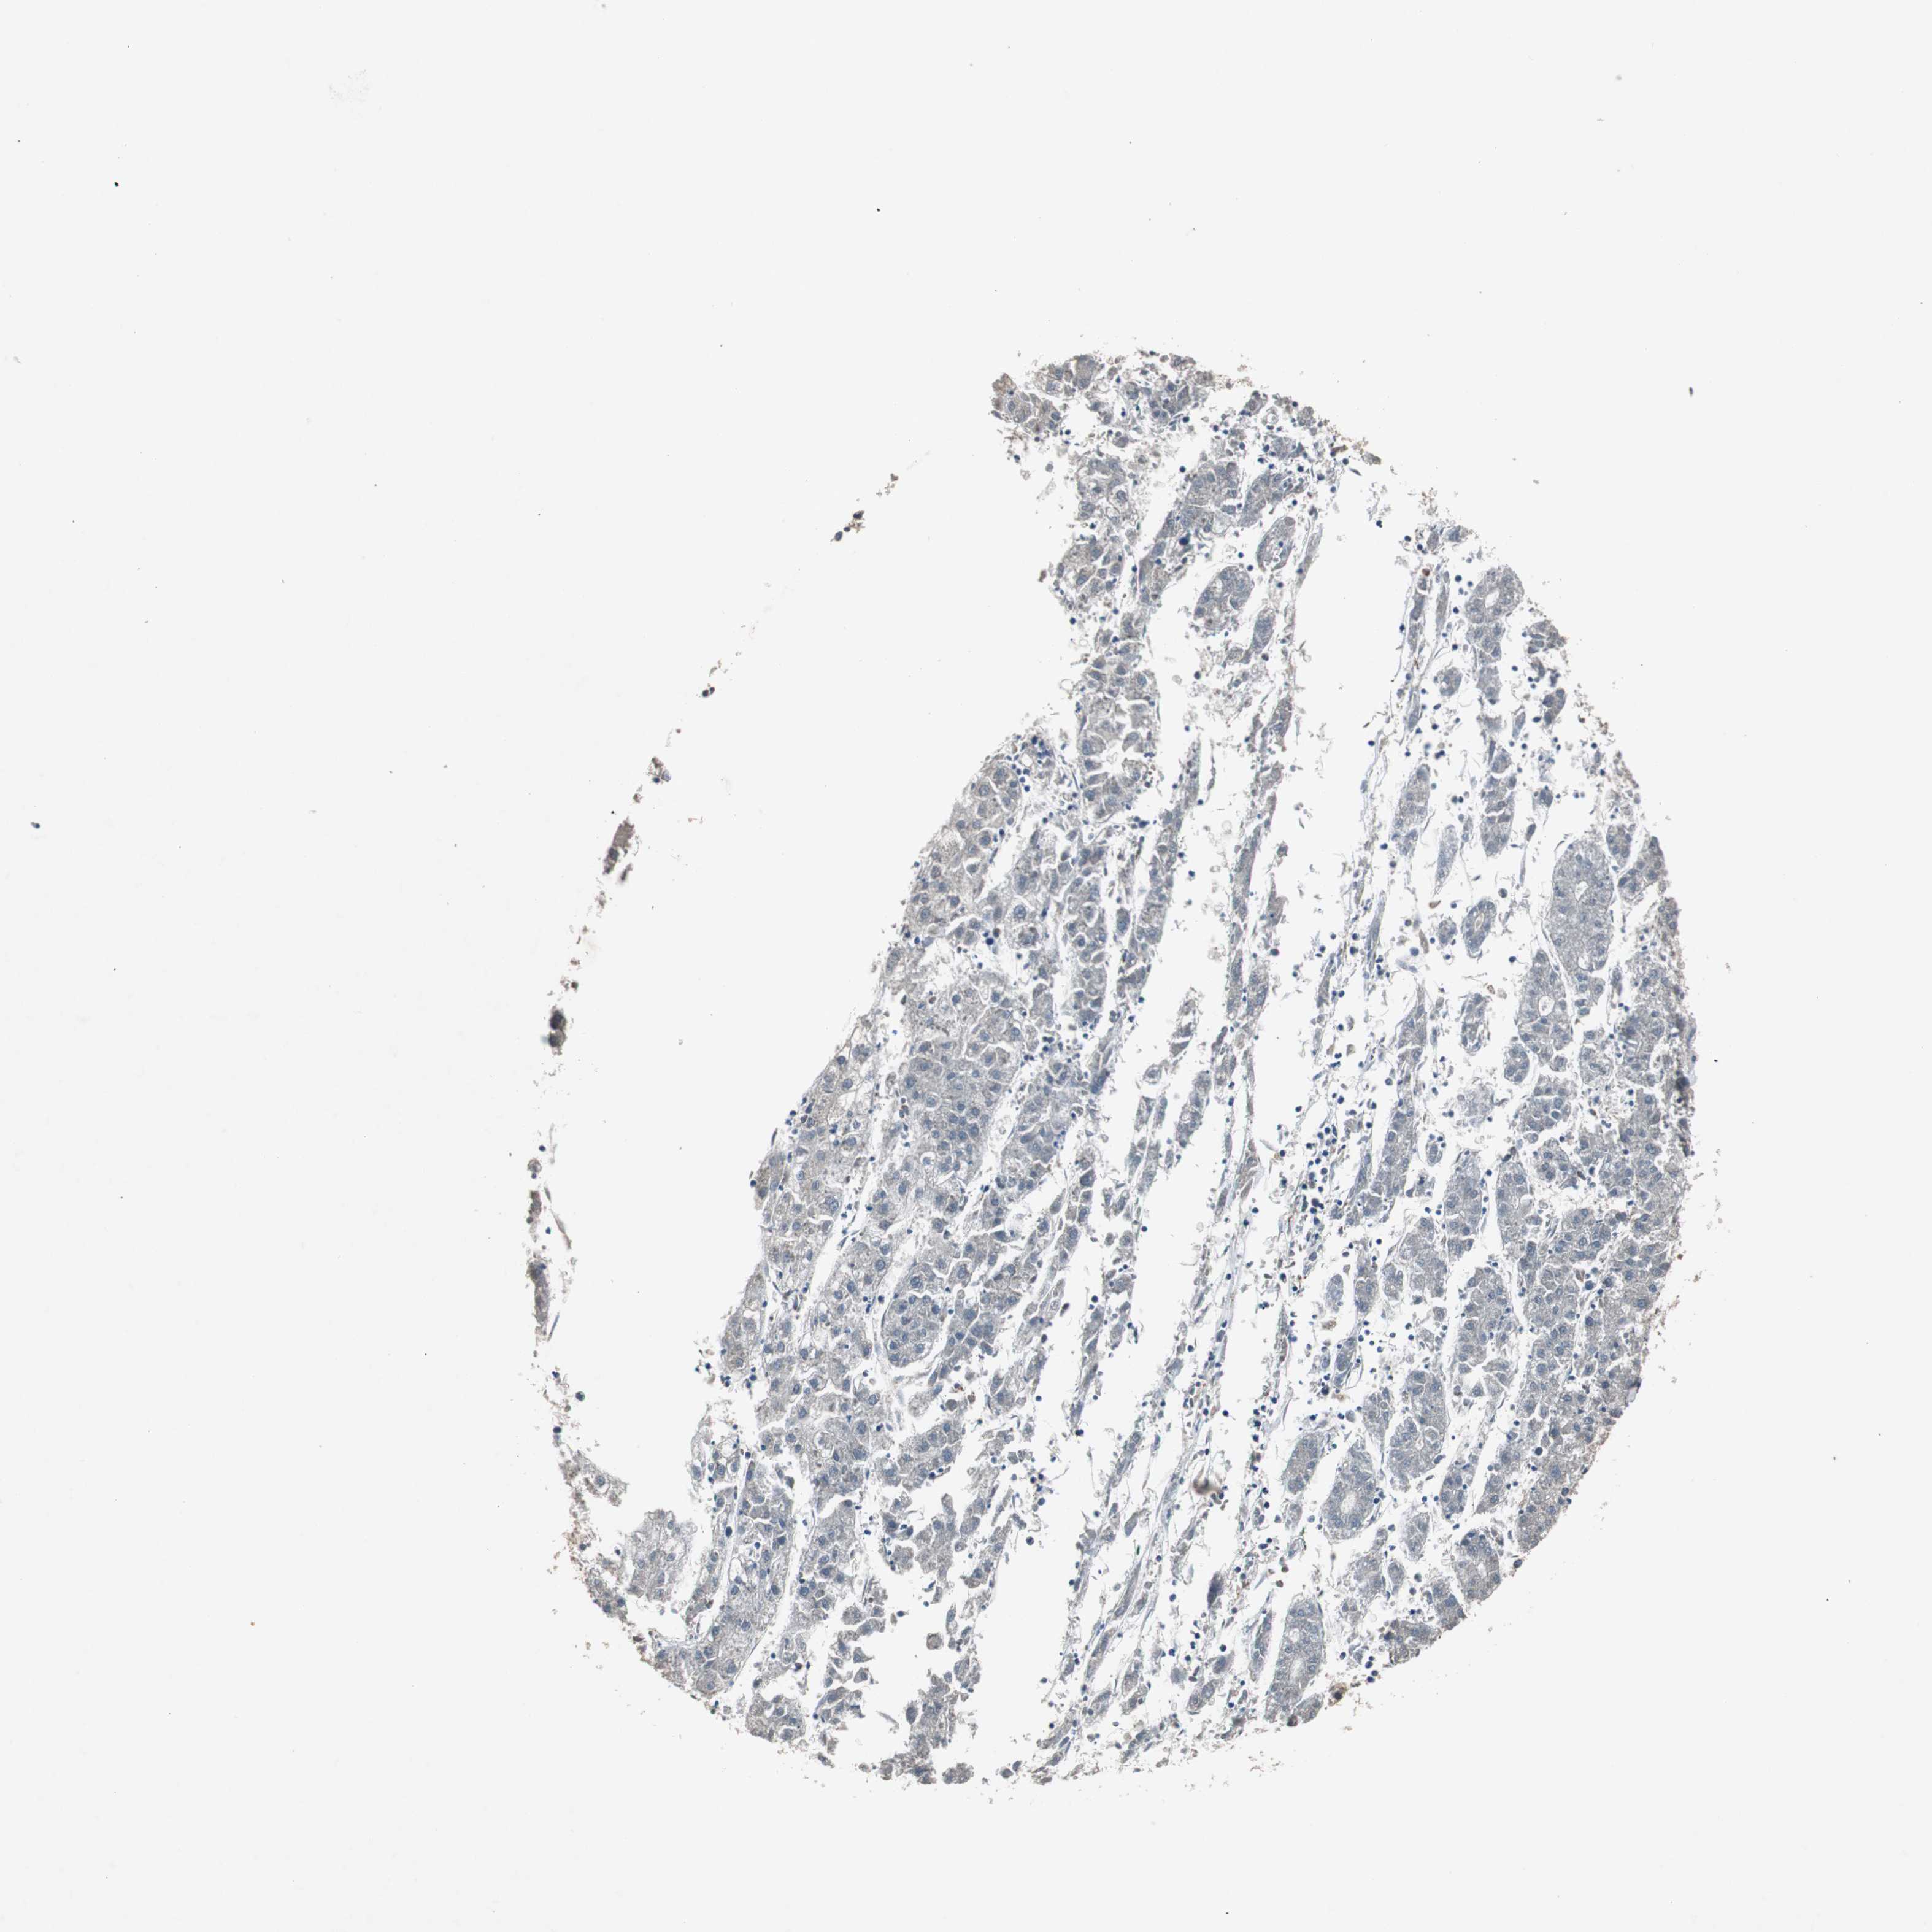

LIVER CANCER - Protein expressioni

A mouse-over function shows sample information and annotation data. Click on an image to view it in a full screen mode. Samples can be filtered based on level of antibody staining by selecting one or several of the following categories: high, medium, low and not detected. The assay and annotation is described here.

Note that samples used for immunohistochemistry by the Human Protein Atlas do not correspond to samples in the TCGA dataset.

Antibody stainingi

Antibody staining in the annotated cell types in the current human tissue is reported as not detected, low, medium, or high, based on conventional immunohistochemistry profiling in selected tissues. This score is based on the combination of the staining intensity and fraction of stained cells.

Each image is clickable and will lead to virtual microscopy that enables deeper exploration of all samples and also displays staining intensity scores, fraction scores and subcellular localization as well as patient and tissue information for each sample.

Antibody HPA007005

Staining

High

Medium

Low

Not detected

Intensity

Strong

Moderate

Weak

Negative

Quantity

>75%

75%-25%

<25%

None

Location

Nuclear

Cytoplasmic/membranous

Cytoplasmic/membranous,nuclear

Cholangiocarcinoma

Carcinoma, Hepatocellular, NOS